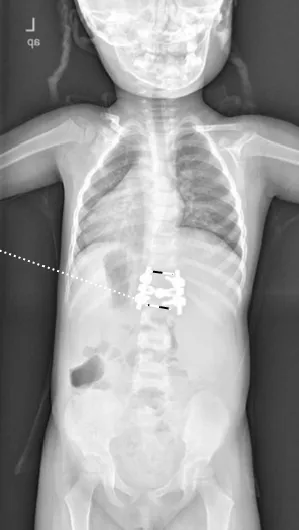

▲ 女,3岁4个月,先天性脊柱侧弯半椎体畸形

▲ 女,7岁,先天性脊柱侧弯半椎体畸形